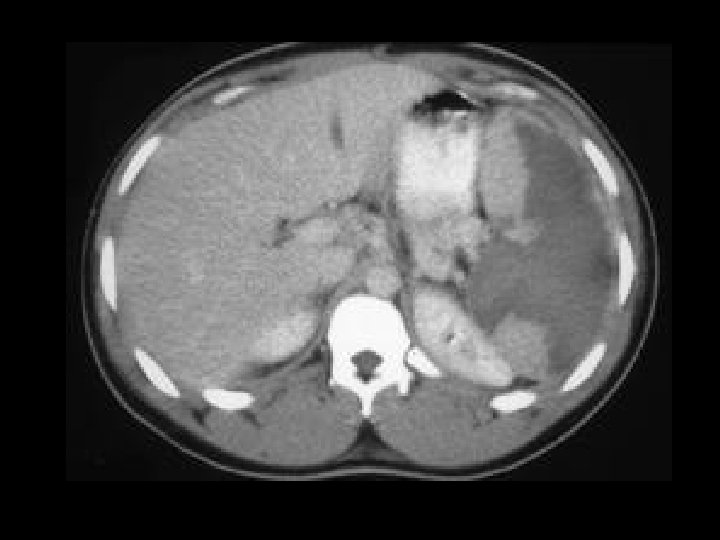

Splenic infarct • Findings: – Large spleen containing a low attenuation geographic lesion extending from the hilus to the periphery • ddx: – NONE! – This is an Aunt Minnie!